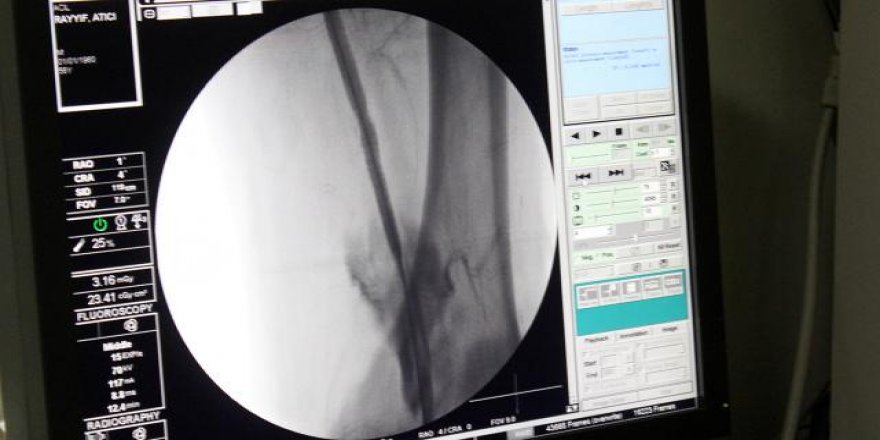

Nihai tasarımlarının, bir prostetik venöz kapakçığın neden olduğu en düşük kayma hızı olduğunu ve bu sonuçlar, etkin bir klinik tedavi şekli potansiyeline sahip olduğunu dile getiren uzmanlar, bu işlemin bir kateter vasıtasıyla anjio altında damara girişim yapılarak kolaylıkla implate edilebilecek bir şekilde tasarladıklarını ifade ediyor.

İşlem minimal invaziv yöntemlerle uygulandığından uzun sürmemekle beraber hasta yatış süreleri mevcut tedavi yöntemlerine göre oldukça düşük olduğu belirtiliyor.